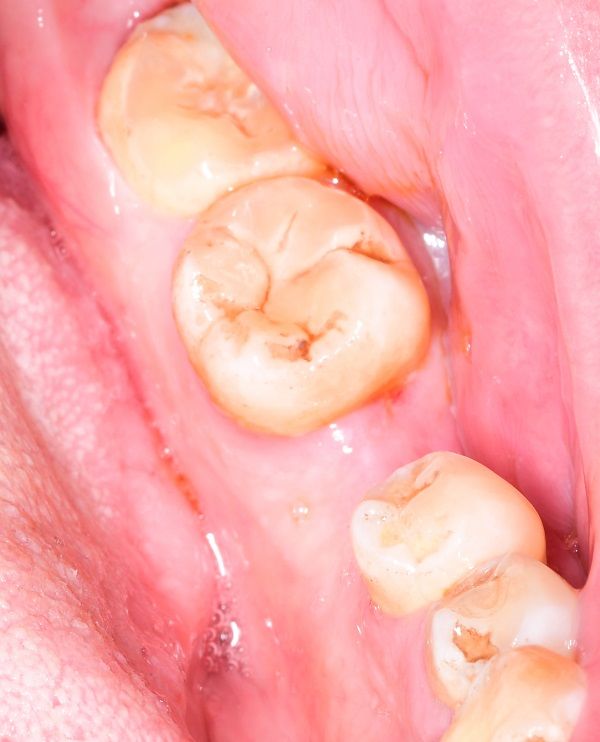

种植牙是将纯钛金属制成的人工牙根(种植体)一端通过微创外科手术植入缺牙部位的牙槽骨内,经过一段愈合期后,人工牙根和颌骨结合,再在人工牙根上镶装义齿。成功的种植牙不仅具有形态逼真、美观、舒适、咀嚼功能好、损伤邻牙等优势,还是目前理想的修复治疗方式,被誉为继乳牙、恒牙后“人类的第三副牙齿”。